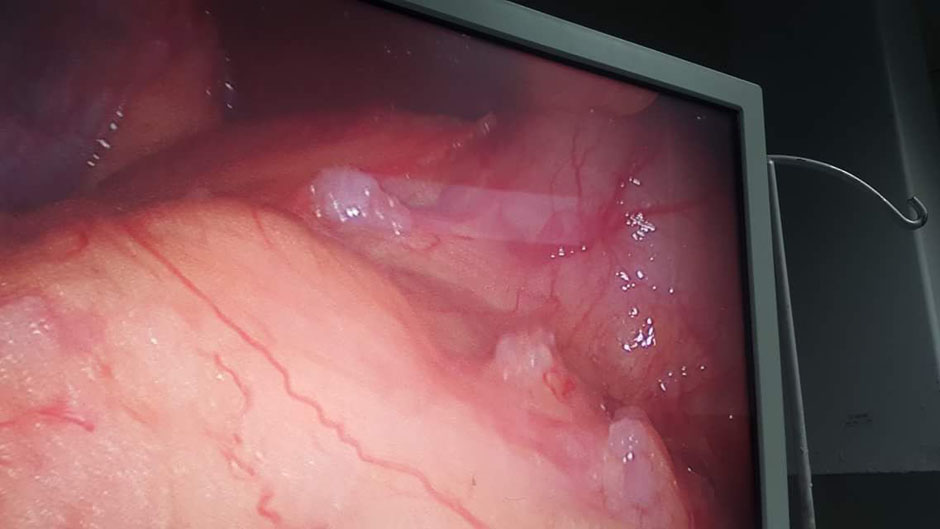

A Young lady who was a small kid...when her mother was operated for a Complex Gastrointestinal condition almost 14 years back by Dr Suddhasattwa Sen suddenly came in with severe blood loss from Gastrointestinal tract with a loss of almost 2 to 3 litres of blood with Shock with fainting . Further stabilisation was done and then extensive investigation revealed not only Piles and GI Ulcers but also SRUS Bleeding ulcers in rectum. A condition called Solitary Rectal Ulcer Syndrome ( a complex and difficult to cure anorectal problem ) . Her hemoglobin dropped to below 7 gm% She finally underwent surgery after 5 days and left home after 2 days post op without any further bleed or problems .